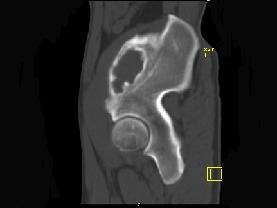

问题 男,34岁,左髂骨疼痛,有皮肤色素沉着,性早熟等,请结合所提供图像,选择最佳答案 ( )

选项 A、内生软骨瘤 B、骨巨细胞瘤 C、畸形性骨炎 D、骨纤维结构不良 E、非骨化性纤维瘤

答案 D